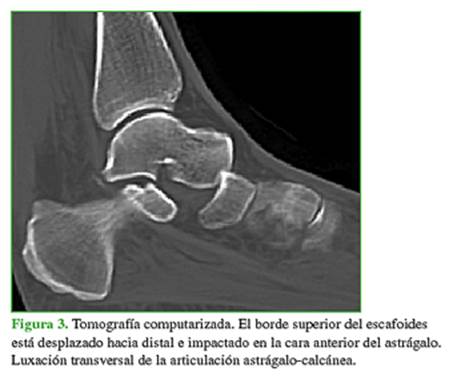

Las radiografías revelaron una luxación periastragalina medial, con evidente incongruencia de las articulaciones astrágalo-escafoidea y astrágalo-calcánea (Figura 2). La tomografía computarizada no mostró lesiones óseas asociadas (Figura 3).